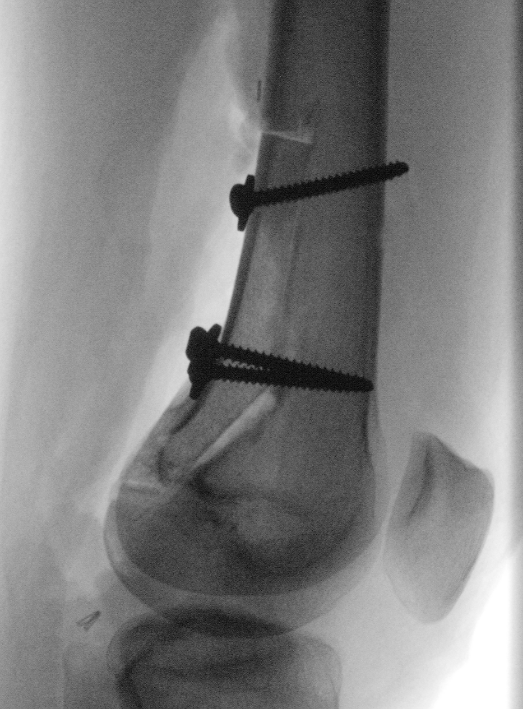

Management

A. Hemicortical resection and posterior hemicortical allograft reconstruction

- hemicortical resection and hemicortical allograft reconstruction

- 22 cases (6 parosteal, 6 peripheral chondrosarcoma, 10 adamantinoma)

- all allografts incorporated

- 6/22 (27%) patients had a fracture of the remaining host hemicortex

- good excellent functional outcome in 21/22 patients

- 111 cases (18 parosteal, 37 adamantinoma)

- 18% host bone fracture

- 7% nonunion

- 7% infection

- 3% allograft fracture